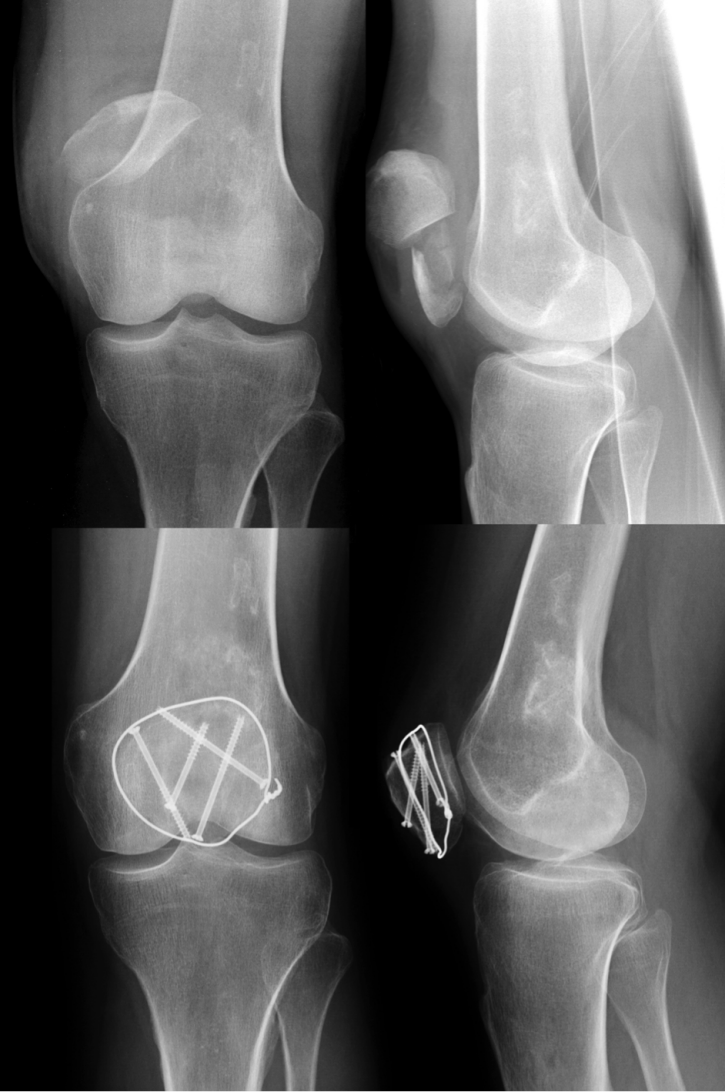

Stable non-displaced fractures (less than 2 mm of dislocation) are suitable for a conservative approach (Figure 2 [Fig. 2]). These cases should be tested up to 60° of flexion under image intensifier control in order to confirm a stable situation with no tendency for dislocation. Braun et al. and Böstman et al. postulated that even comminuted fractures as well as proximal or distal pole fractures can be treated non-operatively if they fit the above mentioned precondition [8], [12]. Exceptions to this rule are chondral or osteochondral fractures in which operative refixation should be obtained even if dislocation meets the mentioned criteria of conservative treatment.

Figure 2: Non-displaced fracture of the proximal patellar pole, which might be suitable for conservative treatment. Notably, these cases should be tested up to 60° of flexion under image intensifier control in order to confirm a stable fracture pattern.

Screw fixation may decrease the risk of fragment dislocation as a result of tension band laxity and serves as a longitudinal stabilization of the fracture (Figure 4 [Fig. 4]). Screws should be applied perpendicular to the fracture line and fit the size of patellar bone (e.g. 3.5 mm cortical screws).

Figure 4: Preoperative X-rays of a comminuted patella fracture (above). 3 months post-surgery using screw fixation and modified tension band (below).

For simple transverse or vertical fractures in patients with adequate bone stock, lag screw fixation can also be considered without tension band wiring to prevent unnecessary dissection of surrounding soft tissue and thus preserving the vascular supply (Figure 5 [Fig. 5]).

Figure 5: Preoperative X-rays of a non-comminuted transverse patella fracture (above). 3 months post-surgery using percutaneous screw fixation (below).